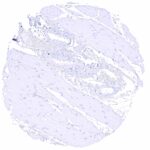

| Brain | Cerebrum | Negative. |

| Cerebellum | Negative. | |

| Respiratory system | Respiratory epithelium | Negative. |

| Lung | Negative. | |